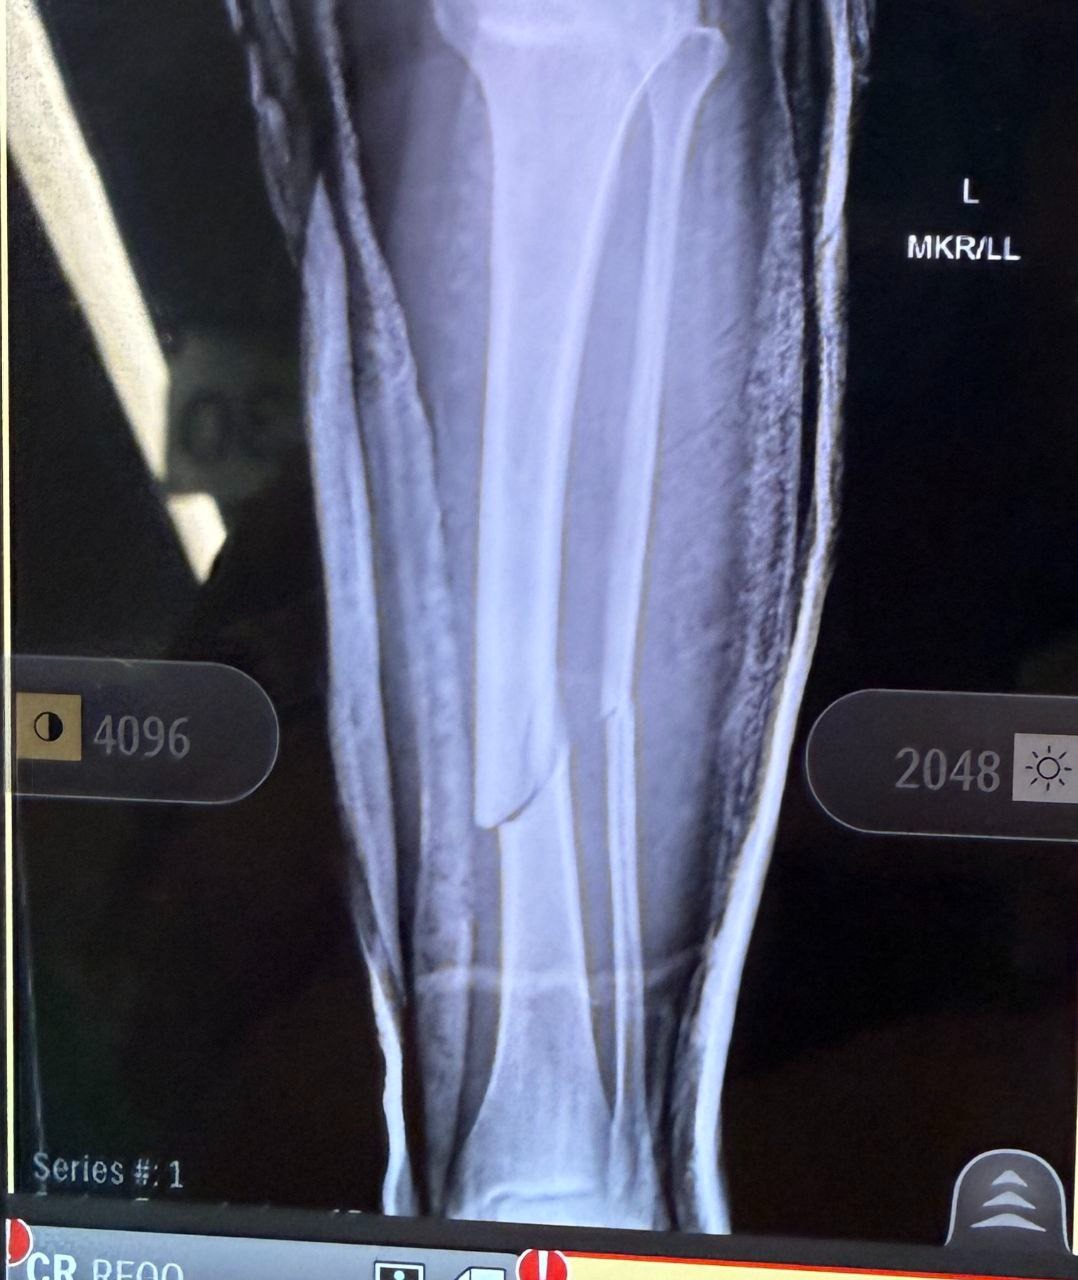

Our family is asking for support for my sister, Gena, who was tragically hit by a car while walking her two beloved golden retrievers in Apopka, Florida. What started as a normal walk turned into a life-changing accident. Gena suffered a severe leg fracture that required surgery, where doctors placed a rod and screws in her leg. She also injured her other foot and is currently in a walking boot. Her recovery will take at least 3–6 months and will require extensive physical therapy. During this time, she cannot fully bear weight and will be unable to work. Her husband was also injured in the accident, adding even more stress to an already overwhelming situation.